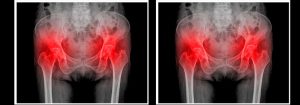

A bursite é a doença inflamatória dessa bolsa, que pode ser ocasionada devido à esforços repetitivos, traumas, infecções, artrites, entre outras causas. O seu diagnóstico é definido pelo médico ortopedista através de testes físicos ou também exames de imagem.

A doença pode acometer qualquer articulação, porém é mais comum nos ombros e quadris. Falaremos hoje especialmente sobre bursite no quadril .